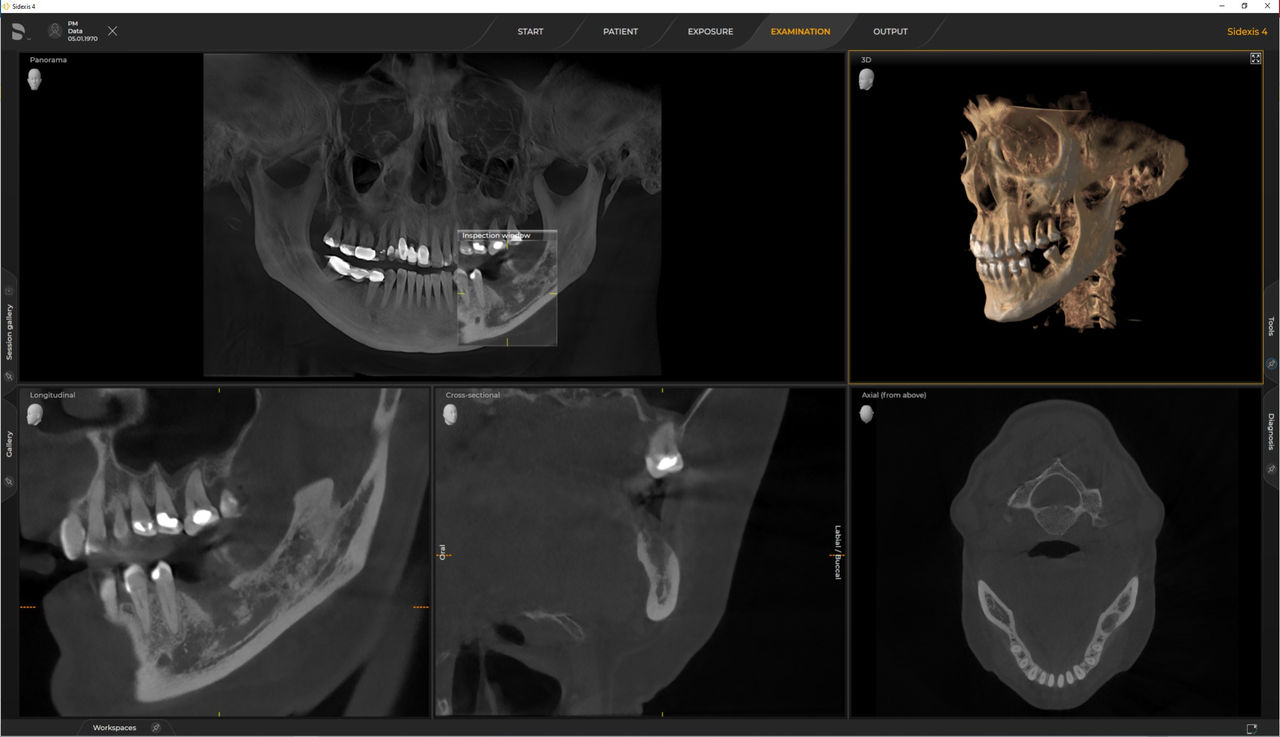

Axeos, el sistema especializado 2D/3D con un gran volumen y alta calidad de imagen para clínicas con una amplia oferta de tratamientos. Desarrollado junto a dentistas y clínicos, Axeos ofrece la gama más completa de funciones de todos los equipos de radiología extraoral de Dentsply Sirona. Además de una excelente calidad de imagen y tamaños de volumen 3D personalizados, el equipo de radiología dental está completamente optimizado para una mayor comodidad del paciente. Axeos no solo proporciona calidad en rendimiento y comodidad, sino también con su galardonado diseño gracias al gabinete integrado para el almacenamiento de posicionadores de mordida y la luz ambiental.

Los numerosos tamaños de volumen garantizan la flexibilidad en la práctica diaria. Examine un área precisa o evalúe la dentición completa, lo que incluye las ATM

Las unidades 3D de Dentsply Sirona funcionan exclusivamente con Sidexis 4. Sin embargo, la migración de datos de Sidexis XG a Sidexis 4 es muy fácil. Sidexis 4 permite una experiencia digital completa con las últimas herramientas.